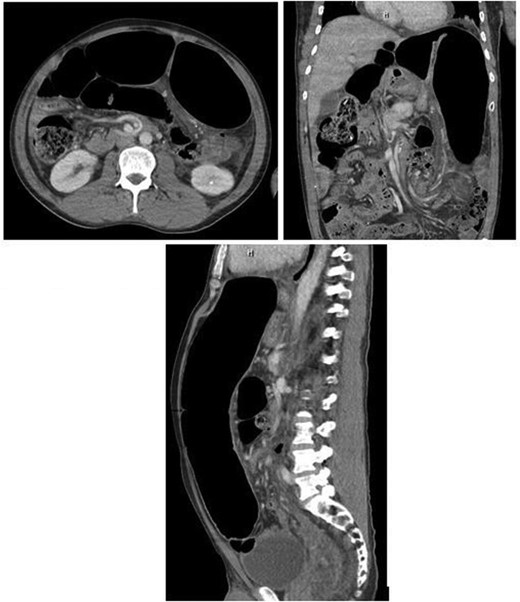

The patient's chest X-ray showed gaseous distention of the colon prompting further investigation. He was then sent for CT scan of his abdomen, revealing distention of the colon with swirling of mesentery in the left lower abdomen, and superior displacement of the sigmoid colon consistent with sigmoid volvulus (Fig. 1).

CT scan findings showing significant sigmoid colonic dilatation with concerns for sigmoid volvulus.